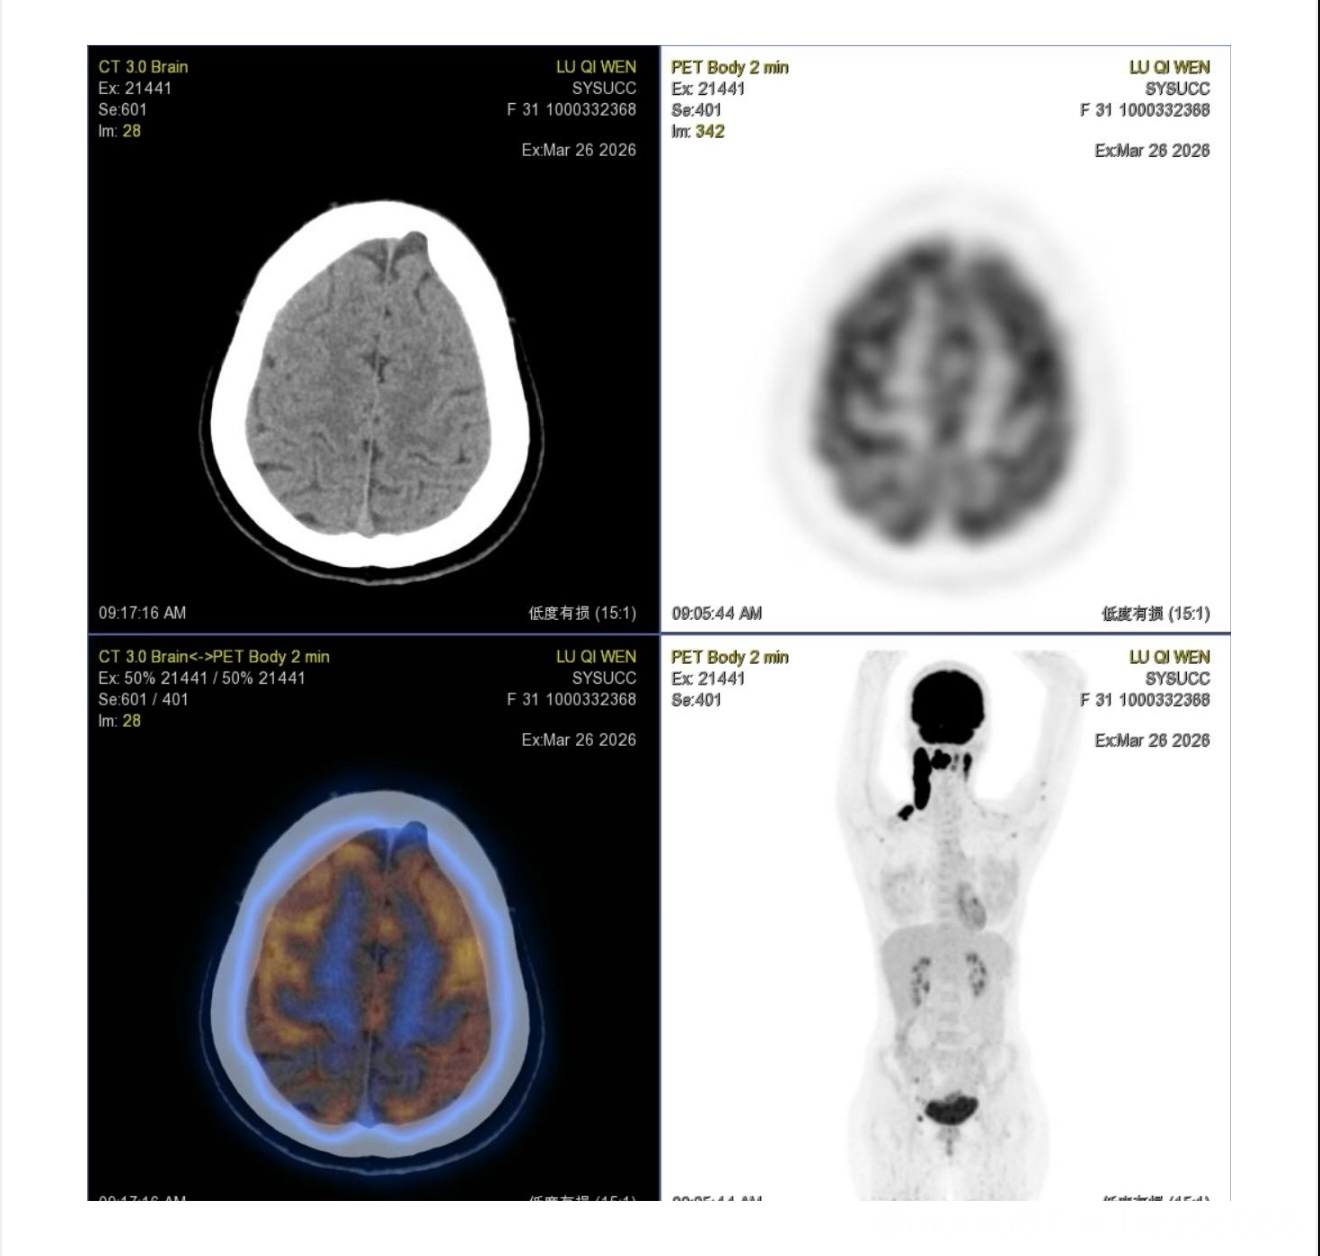

高表达,三期,颈部超大包块和锁骨,盆腔部,血管旁,没等fish 結果,马上开始第一次化疗了,医生好像是用常规的r chop方案 ,也没做什么预防。 哎 ,疑惑啊,希望fish 是好结果,